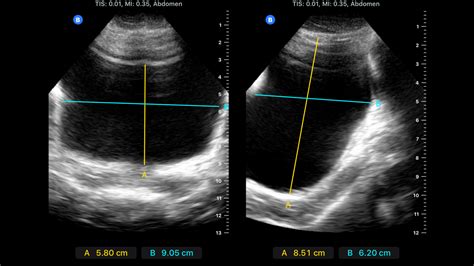

Bladder Post Void Residual Volume Article StatPearls